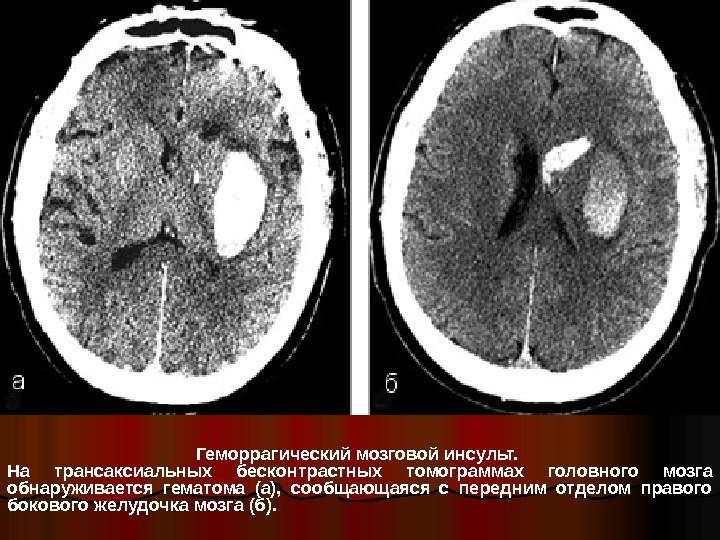

Геморрагический мозговой инсульт. На трансаксиальных бесконтрастных томограммах головного мозга обнаруживается гематома (а), сообщающаяся с передним отделом правого бокового желудочка мозга (б).